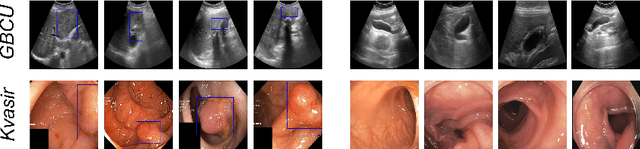

Abstract:We focus on the problem of Gallbladder Cancer (GBC) detection from Ultrasound (US) images. The problem presents unique challenges to modern Deep Neural Network (DNN) techniques due to low image quality arising from noise, textures, and viewpoint variations. Tackling such challenges would necessitate precise localization performance by the DNN to identify the discerning features for the downstream malignancy prediction. While several techniques have been proposed in the recent years for the problem, all of these methods employ complex custom architectures. Inspired by the success of foundational models for natural image tasks, along with the use of adapters to fine-tune such models for the custom tasks, we investigate the merit of one such design, ViT-Adapter, for the GBC detection problem. We observe that ViT-Adapter relies predominantly on a primitive CNN-based spatial prior module to inject the localization information via cross-attention, which is inefficient for our problem due to the small pathology sizes, and variability in their appearances due to non-regular structure of the malignancy. In response, we propose, LQ-Adapter, a modified Adapter design for ViT, which improves localization information by leveraging learnable content queries over the basic spatial prior module. Our method surpasses existing approaches, enhancing the mean IoU (mIoU) scores by 5.4%, 5.8%, and 2.7% over ViT-Adapters, DINO, and FocalNet-DINO, respectively on the US image-based GBC detection dataset, and establishing a new state-of-the-art (SOTA). Additionally, we validate the applicability and effectiveness of LQ-Adapter on the Kvasir-Seg dataset for polyp detection from colonoscopy images. Superior performance of our design on this problem as well showcases its capability to handle diverse medical imaging tasks across different datasets. Code is released at https://github.com/ChetanMadan/LQ-Adapter